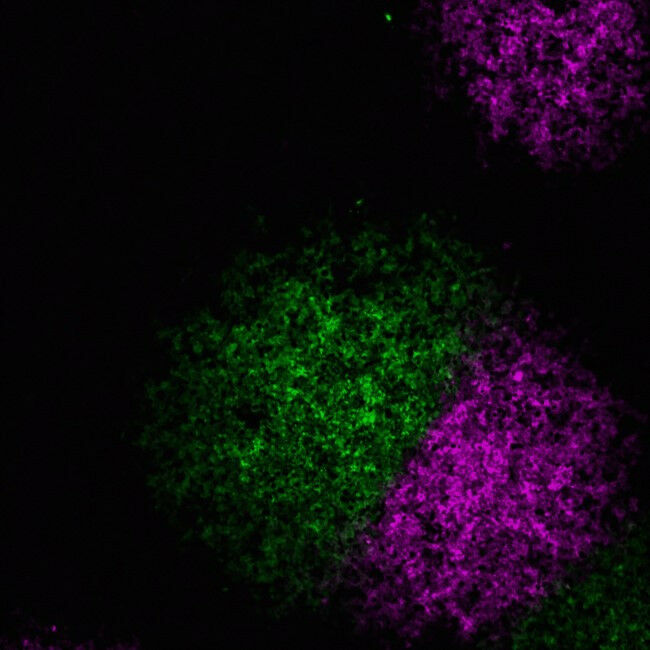

Two influenza A viruses, one labelled magenta and one labelled green, have spread rapidly across this sheet of cells, but are unable to cross into each other’s territory. o Image credit: Anna Sims, MRC-University of Glasgow Centre for Virus Research.

Two influenza A viruses, one labelled magenta and one labelled green, have spread rapidly across this sheet of cells, but are unable to cross into each other's territory. o Image credit: Anna Sims, MRC-University of Glasgow Centre for Virus Research. This winter many of us will experience the symptoms caused by colds and flu. Coughs, sneezes, sore throats and fevers are all caused by unwelcome viral visitors who temporarily setup home in our respiratory systems. But what's really happening inside our bodies as viruses fight to overpower our immune systems - and each other - in a bid to succeed? Now, scientists at the MRC-University of Glasgow Centre for Virus Research (CVR) have revealed more about the hidden world of respiratory viral infection. Their new research, published in PLOS Biology, highlights the secret viral dramas going on inside our throats and lungs. In this new study, researchers show how one of the most common and potentially serious winter viruses - the influenza A virus - creates and defends microscopic territories inside its host.